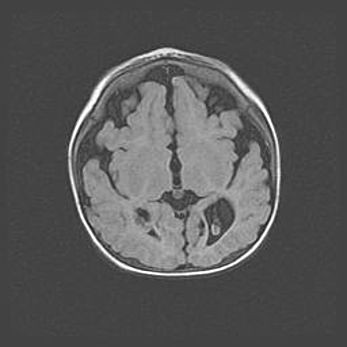

Множественные кисты обоих полушарий головного мозга, наибольшая из них в правой затылочной области. Ассиметричная атрофическая гидроцефалия.

Возраст: 7 месяцев

Вес: 5660 г

Пол: мужской

Окружность головы: 41,5 см

Срок гестации: 28-29 недель

Кисты головного мозга развиваются в результате многоочаговых некрозов вещества мозга и возникают вследствие перенесенной перинатальной инфекции, менингитов, энцефалитов, асфиксии, родовой травмы, расстройств мозгового кровообращения различного генеза. Образованию кист в веществе головного мозга плодов и новорожденных способствуют такие факторы, как высокое содержание в нем воды, недостаточная (или отсутствие) миелинизация и слабая астроглиальная реакция на повреждение.

Кисты могут сочетаться с гидроцефалией и другими поражениями головного мозга.